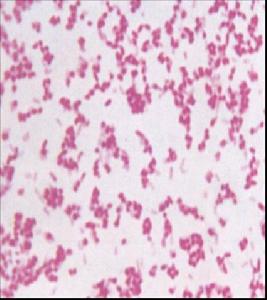

小腸結腸炎耶爾森菌腸桿菌科耶爾森菌屬,為革蘭氏陰性小桿菌,有毒菌株多呈球桿狀,無毒株以桿狀多見。對營養要求不高,能在麥康凱瓊脂上生長,但較其他腸道桿菌生長緩慢,培養的最適宜溫度為28℃,最適pH值為7~8,初次培養菌落為光滑型,通過傳代接種後菌落可能呈粗糙型。

小腸結腸炎耶爾森菌的革蘭氏染色細菌的防治